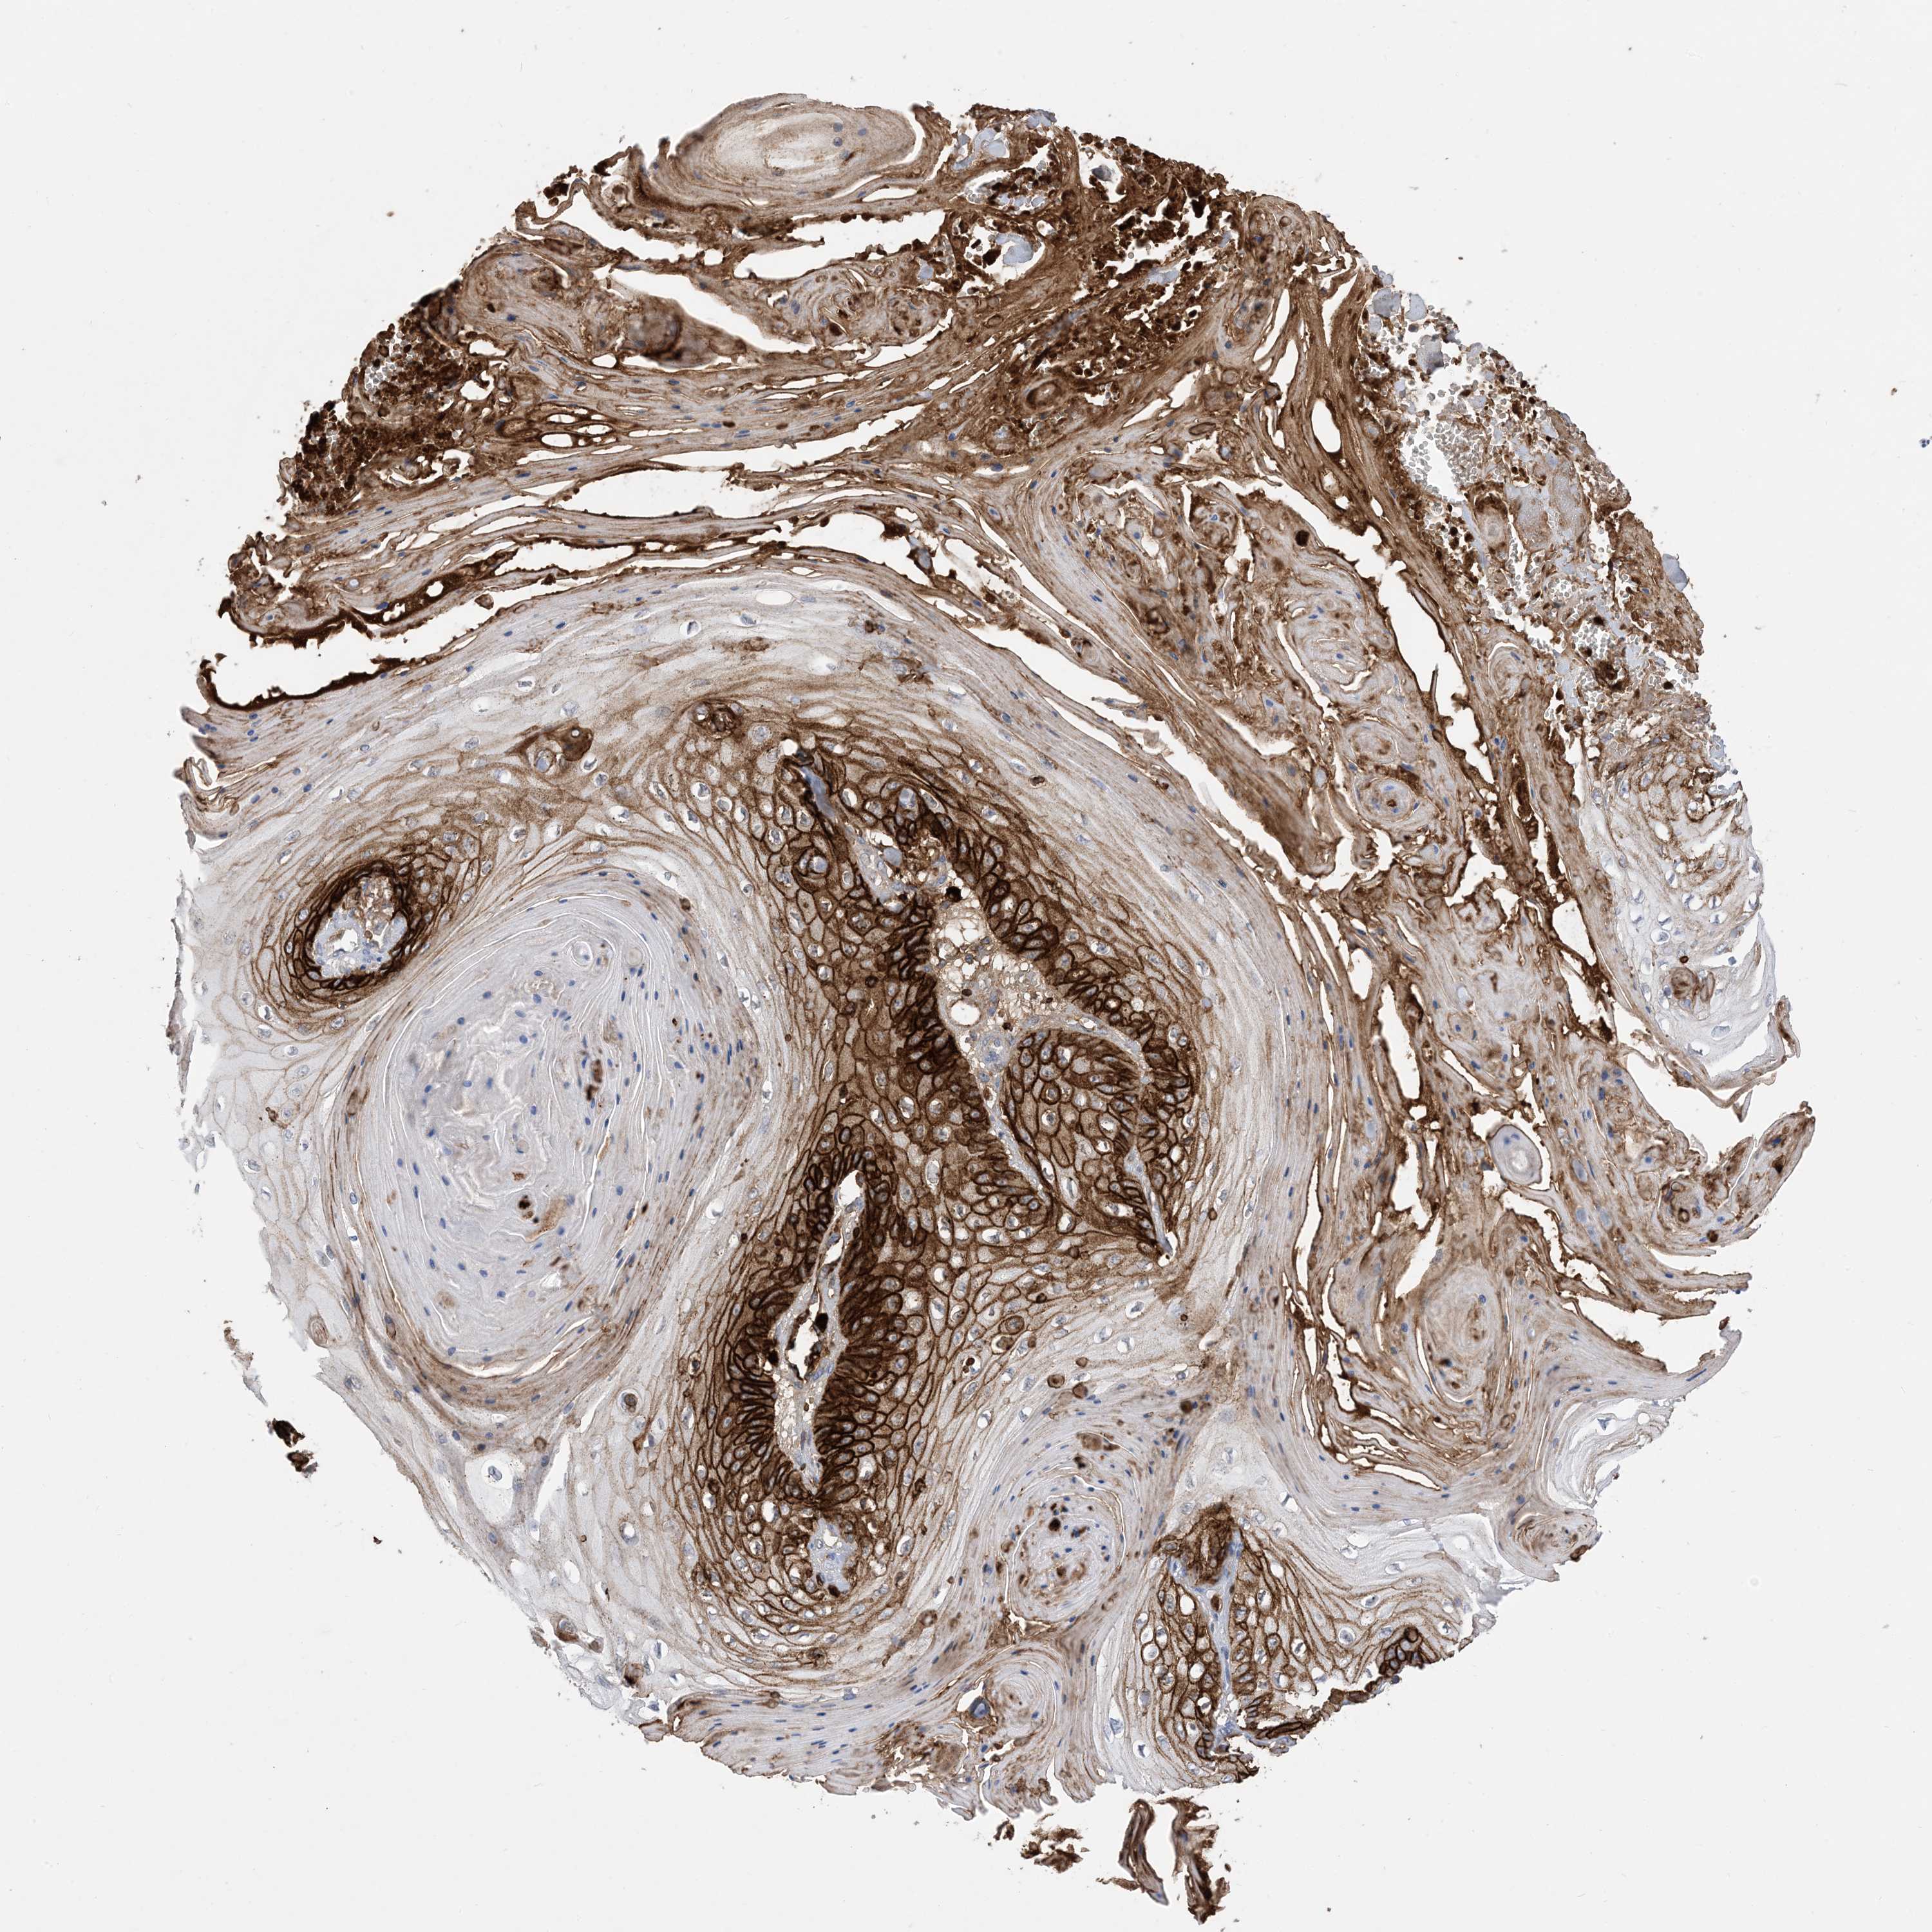

Basal cell and squamous cell cancer

SKIN CANCER - Protein expressioni

A mouse-over function shows sample information and annotation data. Click on an image to view it in a full screen mode. Samples can be filtered based on level of antibody staining by selecting one or several of the following categories: high, medium, low and not detected. The assay and annotation is described here.

Antibody stainingi

Antibody staining in the annotated cell types in the current human tissue is reported as not detected, low, medium, or high, based on conventional immunohistochemistry profiling in selected tissues. This score is based on the combination of the staining intensity and fraction of stained cells.

Each image is clickable and will lead to virtual microscopy that enables deeper exploration of all samples and also displays staining intensity scores, fraction scores and subcellular localization as well as patient and tissue information for each sample.

Antibody HPA049265

Antibody CAB037328

Staining

High

Medium

Low

Not detected

Intensity

Strong

Moderate

Weak

Negative

Quantity

>75%

75%-25%

<25%

None

Location

Nuclear

Cytoplasmic/membranous

Cytoplasmic/membranous,nuclear

Squamous cell carcinoma, NOS